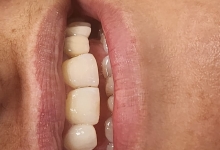

Clinica LUY ESTHETIC ART defineste parodontoza ca fiind rezultatul direct al placii dentare, care se depune pe suprafata dintilor, dar si in apropiere de marginea gingivala. Aceasta boala duce la pierderea dintilor, chiar daca ei sunt aparent sanatosi si nu prezinta carii. Edentatiile, afecteaza vorbirea, aspectul, dar si capacitatea de a mesteca.

Boala parodontala are un caracter progresiv. Pentru cazurile mai grave, recomandam tratamentul parodontal chirurgical rezectiv sau regenerativ.